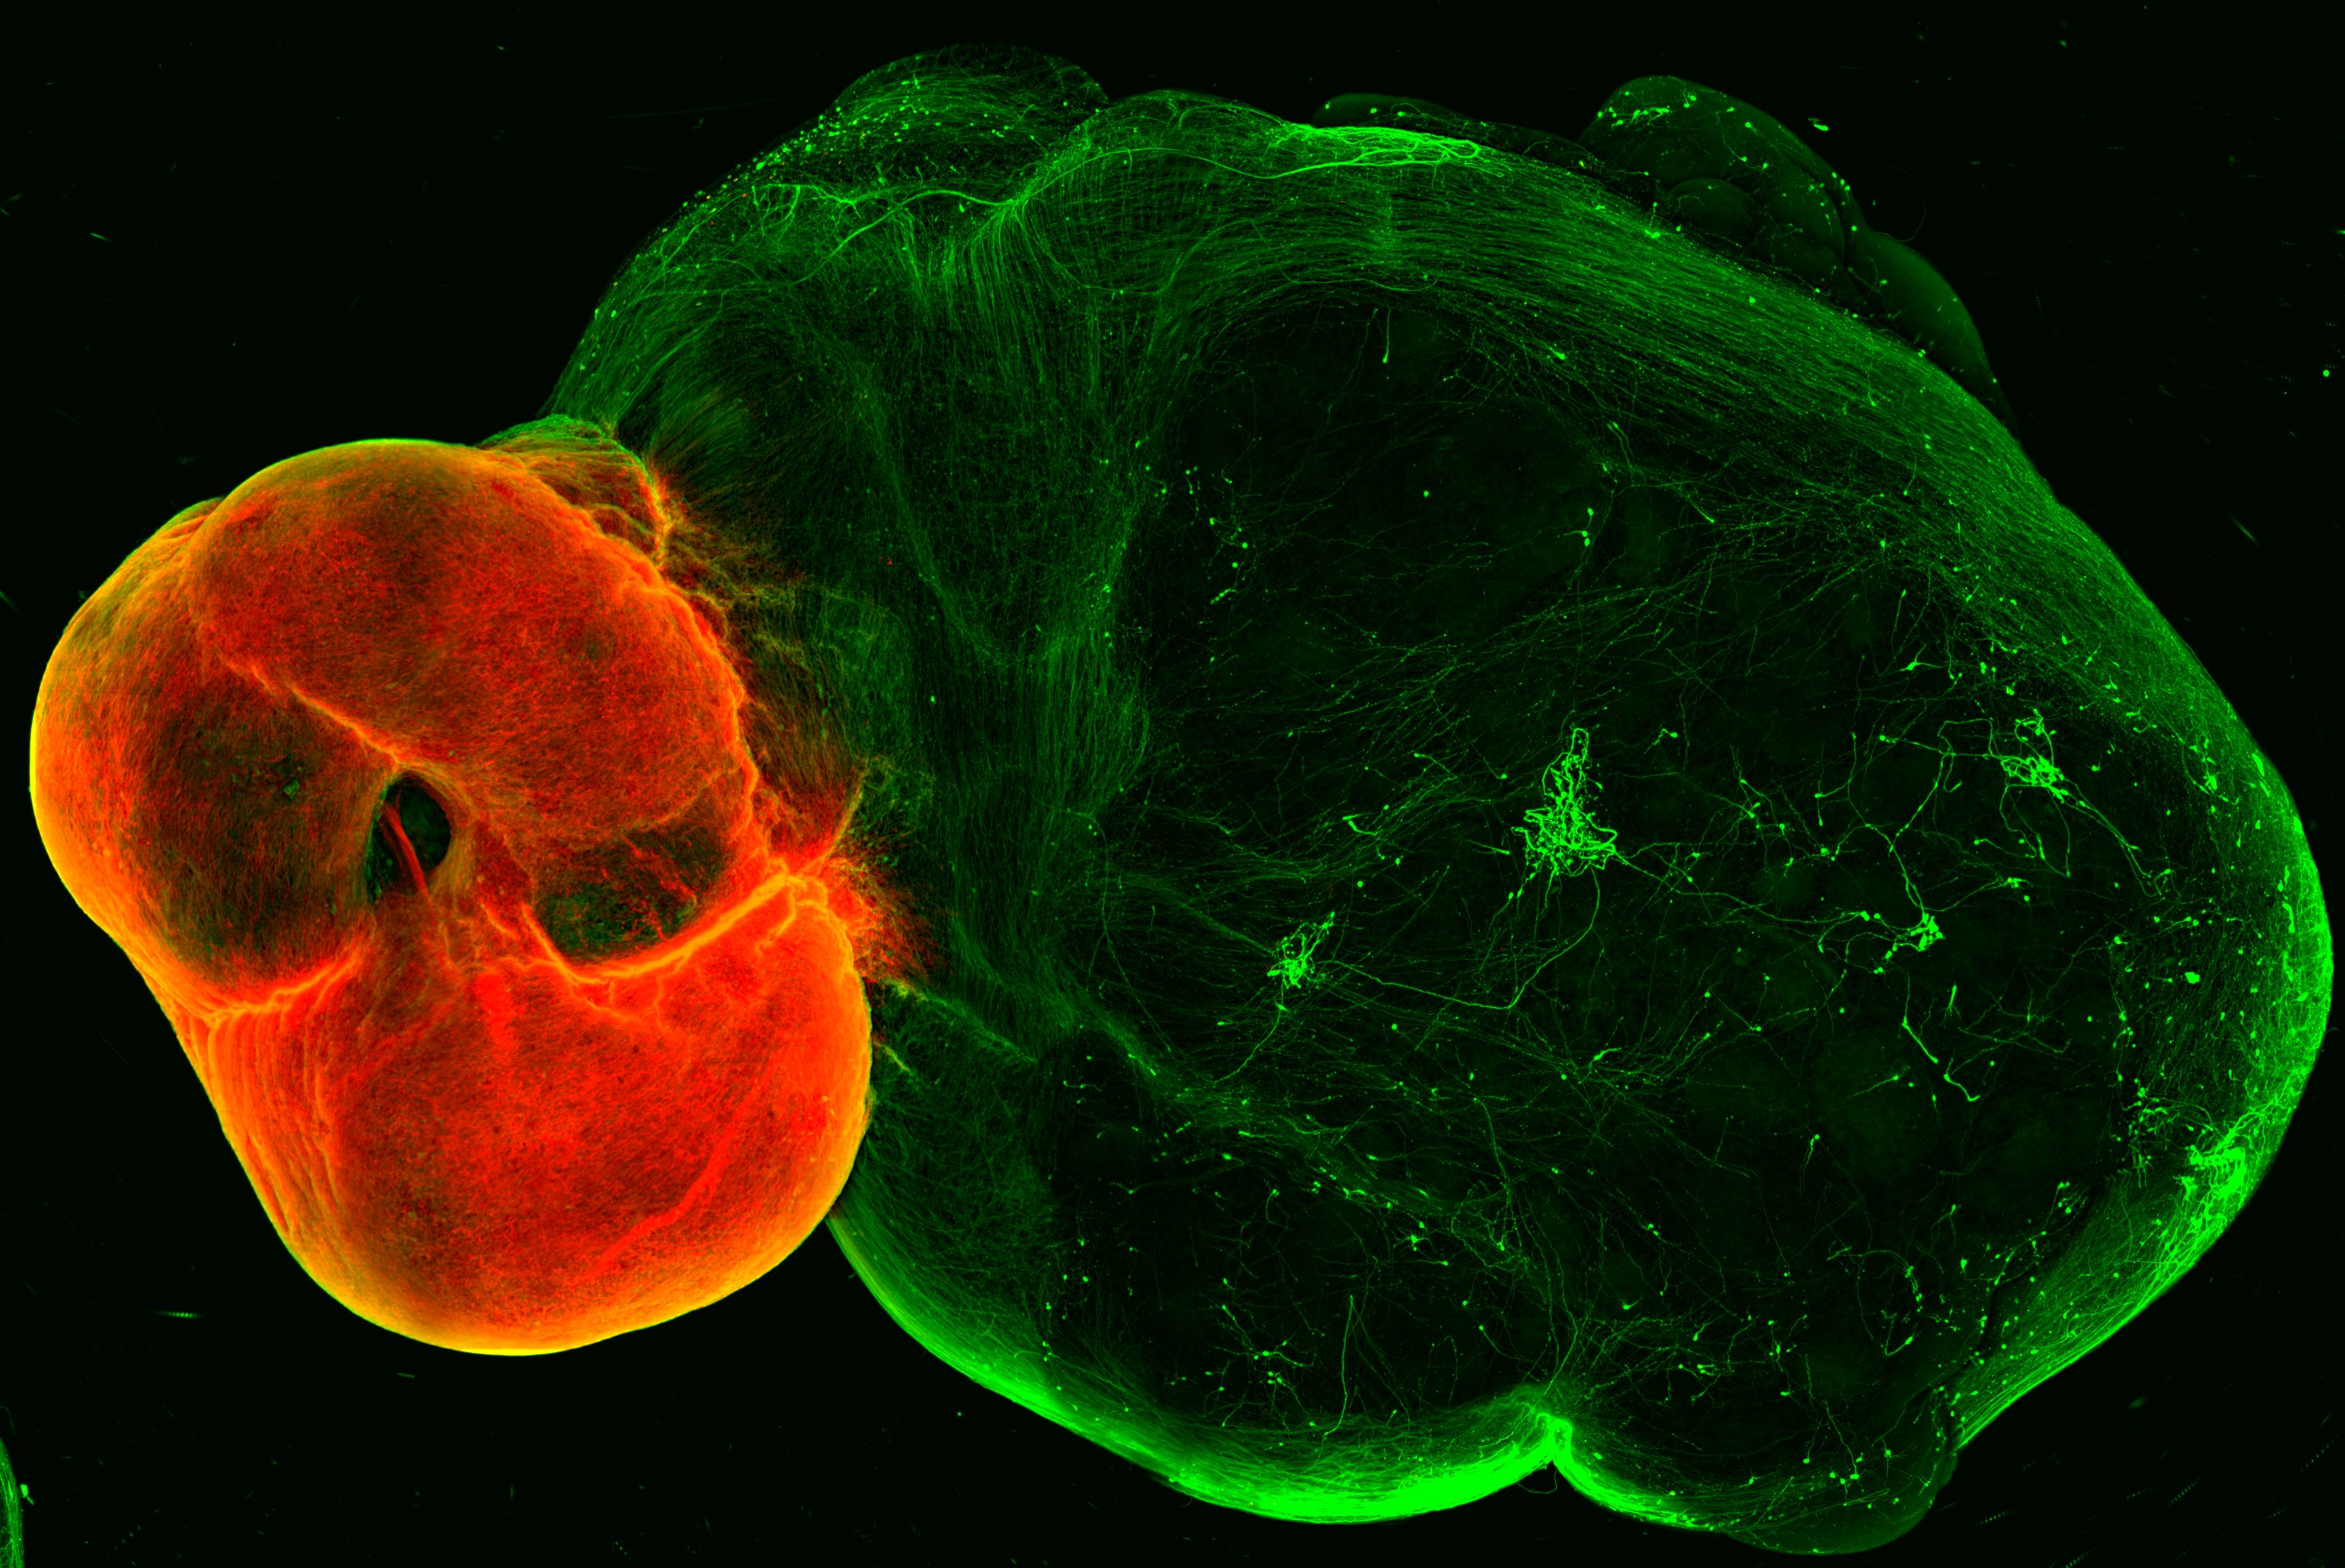

The team first developed organoid models of the so-called ventral midbrain, striatum and cortex – the regions linked by neurons in the dopaminergic system – and then developed a method for fusing these organoids together. As happens in the human brain, the dopaminergic neurons of the midbrain organoid send out projections to the striatum and the cortex organoids. “Somewhat surprisingly, we observed a high level of dopaminergic innervation, as well as synapses forming between dopaminergic neurons and neurons in striatum and cortex”, Reumann recalls.

To assess whether these neurons and synapses are functional, the team collaborated with Cedric Bardy’s group at SAHMRI and Flinders University, Australia, to investigate if neurons in this system would start to form functional neural networks. And indeed, when the researchers stimulated the midbrain which contains dopaminergic neurons, neurons in the striatum and cortex responded to the stimulation. “We successfully modelled the dopaminergic circuit in vitro, as the cells not only wire correctly, but also function together”, Reumann sums up.